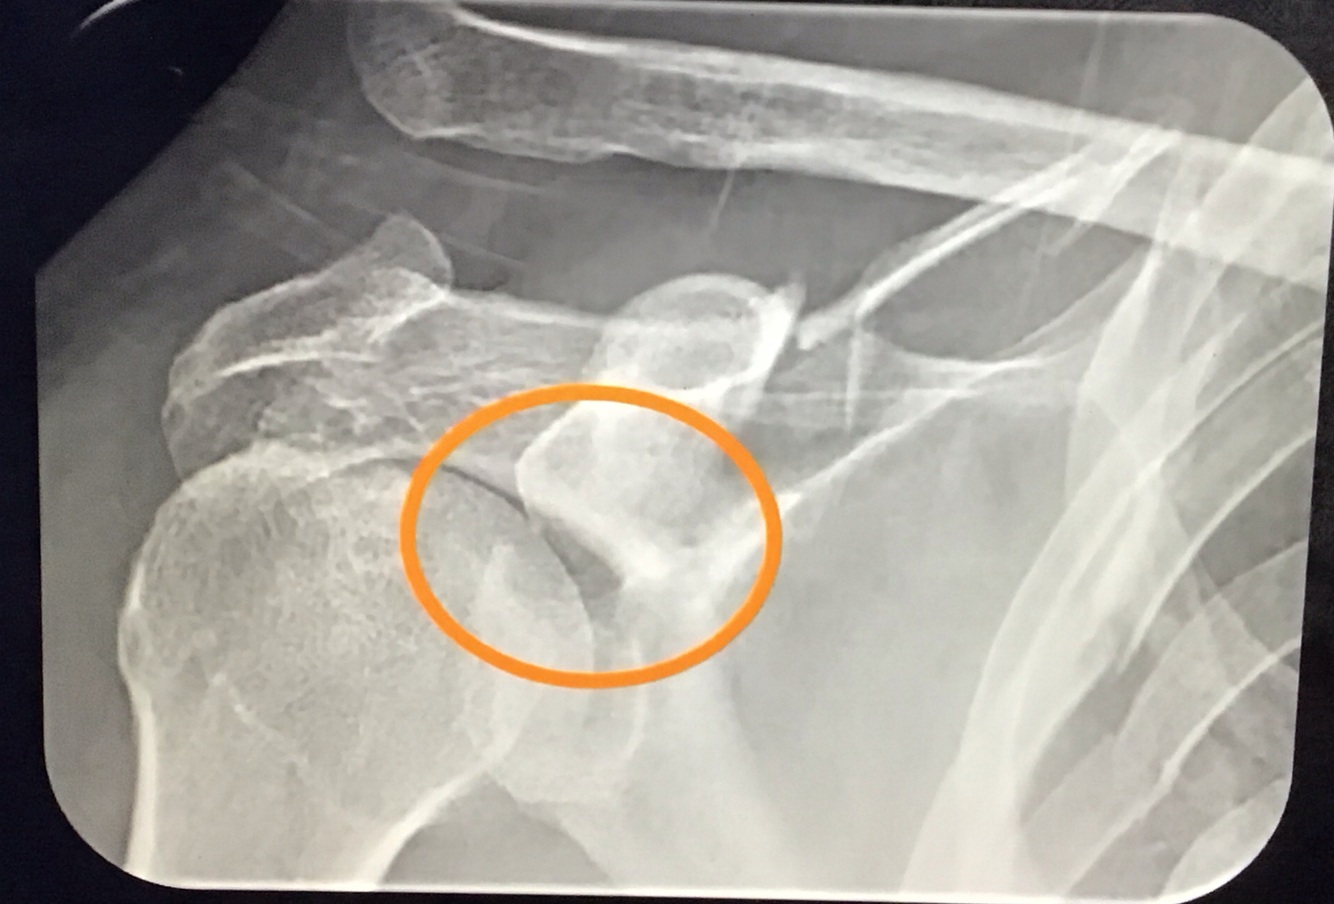

17

Q

O que pensar nos casos em que o paciente tem LAC mas a distância CC está normal? O que fazer?

A

Avaliar fx da base do coracoide!

A LAC ocorreu pq o coracoide subiu junto, e não pq o ligamento rompeu

Deve-se fazer a incidência de STRIKER NOTCH